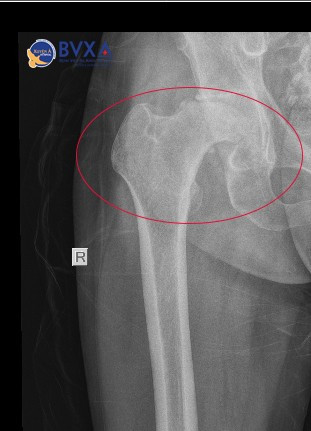

Bệnh nhân P.H.A. (38 tuổi, Vĩnh Long) đến Bệnh viện Đa khoa Xuyên Á Vĩnh Long khám trong tình trạng đau khớp háng phải từ 1 năm nay, đã điều trị nội khoa (uống thuốc giảm đau, kháng viêm…) nhưng vẫn không thuyên giảm, mức độ đau ngày càng tăng dần, đi lại khó khăn, khó tham gia các hoạt động thường ngày, chân phải ngắn hơn chân trái khoảng 2cm.

Bệnh nhân đến khám tại Bệnh viện Đa khoa Xuyên Á Vĩnh Long, kết quả chụp X-quang cho thấy rõ hình ảnh hoại tử chỏm xương đùi phải. Người bệnh được các bác sĩ tư vấn cụ thể về tình trạng sức khỏe và phương án phẫu thuật tối ưu nhất là thay khớp háng toàn phần qua lối trên trực tiếp.

Thay khớp háng do hoại tử vô khuẩn chỏm xương đùi trên phim chụp - Ảnh BVCC